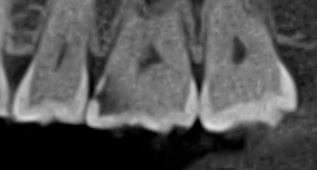

Ми розуміємо, наскільки важлива деталізація в ендодонтії та терапевтичному лікуванні.

Завдяки флагманському обладнанню PLANMECA, ми отримуємо знімки з мінімальним рівнем шумів та

високою роздільною здатністю, що дозволяє чітко візуалізувати морфологію кореневих каналів,

приховані каріозні порожнини та стан періапікальних тканин.